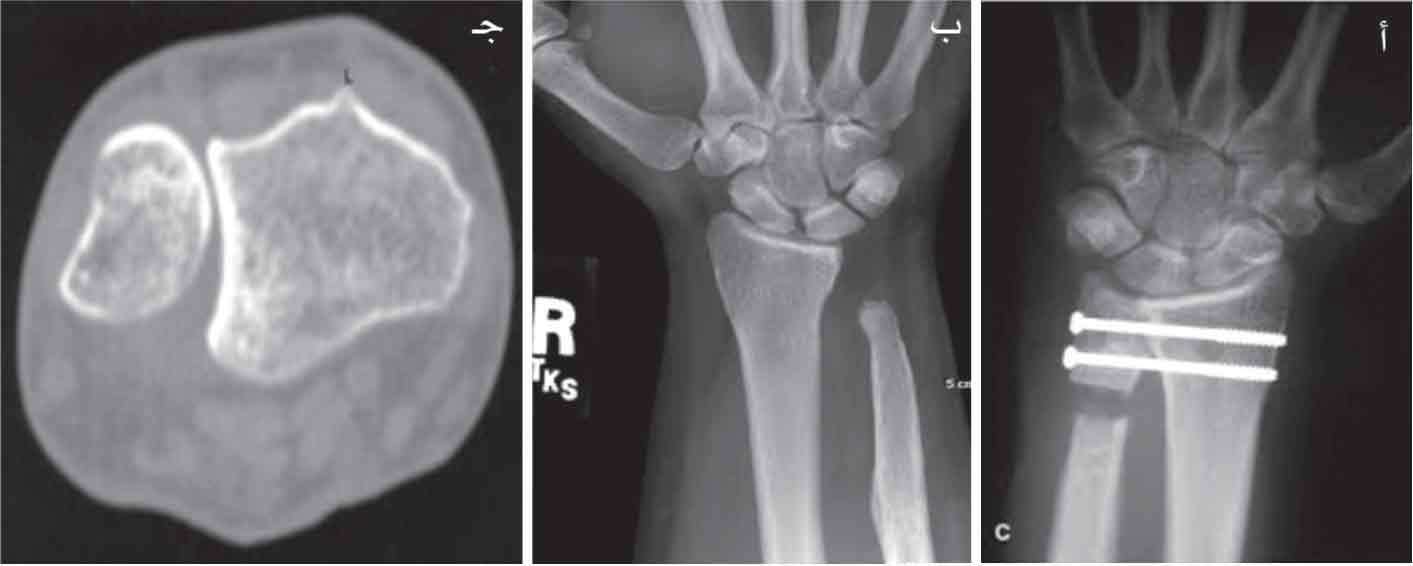

(الشكل 12) أ- عملية كابانجي، ب- استئصال رأس الزند، ج- تصوير مقطعي محوسب للمفصل الكعبري الزندي (تصلب مع انقراص مفصلي).